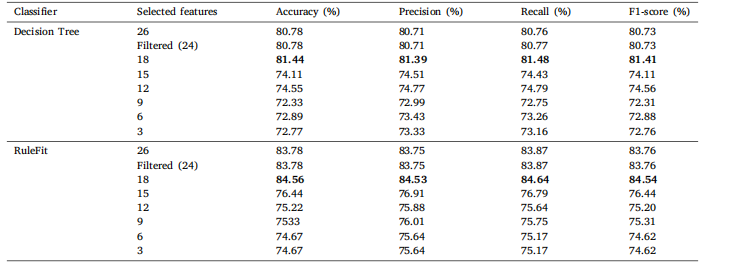

Table 9Classification results of Brain MRI Images for Brain Tumor Detection on comprehensive set of statistical features with varying feature countsfor DT and RuleFit.

表9 基于不同数量统计特征的脑肿瘤检测脑部MRI图像分类结果(针对决策树(DT)和RuleFit模型)。

Table 10Classification results of Lung and Colon Cancer Histopathological Images on the comprehensive set of statistical features with varying featurecounts for DT and RuleFit.

表10 基于不同数量统计特征的肺和结肠癌病理组织图像分类结果(针对决策树(DT)和RuleFit模型)。